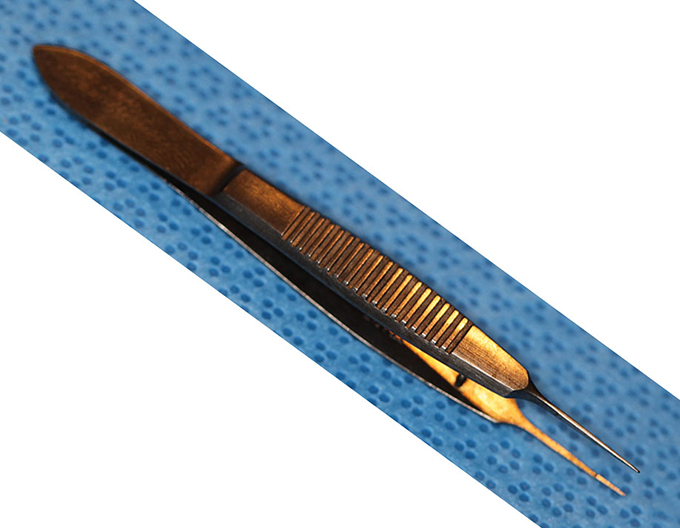

Forcep Thumb, Utrata

(aka Utrara Forceps)

catalog number: Storz 2-719

Typical Use(s): Capsulorhexis; Remove stuck haptic from IOL optic